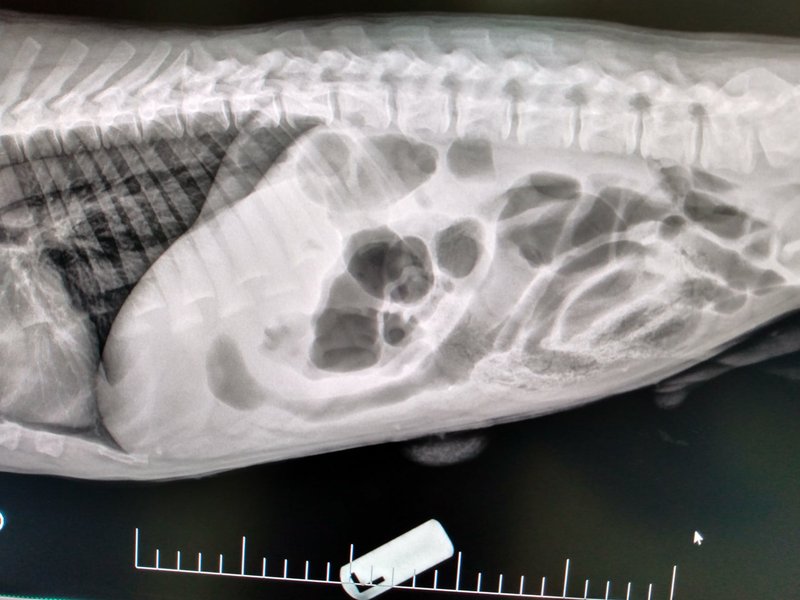

Diagnostic testing plays a vital role in understanding your pets health.

Early detection allows us to identify concerns sooner, improve treatment outcomes, and establish baseline information for future care.

As a pet parent, you may notice when something “isn’t quite right” with your pet, but determining the cause is not always straightforward. That is where diagnostic testing comes in. At Silver Creek Animal Clinic, our veterinary team is committed to providing a complete picture of your pets health through advanced laboratory and diagnostic services, helping us make informed decisions and deliver the best possible care.